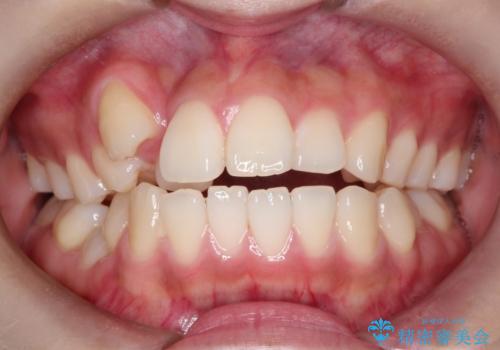

- 出っぱによる口元の閉じにくさを主訴に来院されました。上顎の出っ歯と上下顎叢生も認められたため、上下顎両側4番抜歯を行い、ワイヤー矯正で治療する治療計画を立てました。

上顎にはMI(マイクロインプラント)を埋入して固定源とすることで出っ歯の改善を図りました。

少しスペースクローズに時間がかかりましたが、MIを用いたワイヤー矯正で

主訴である出っ歯と叢生が改善されました。口も閉じやすくなり、スッキリとした口元になりました。